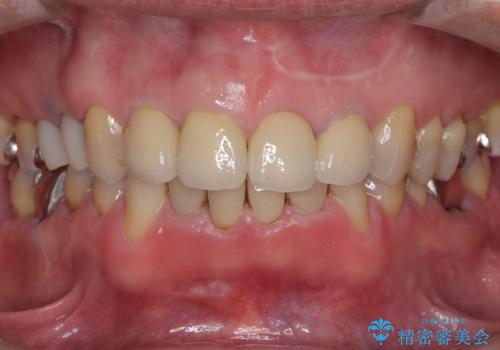

左上1は抜歯と同時にインプラントを埋入し、骨や歯ぐきの形態を維持しながら治療を進めました。左上2は歯根端切除術により感染部位を除去し、保存治療を実施。右上1・2も含めた前歯4本をセラミッククラウンで修復し、自然な色調と形態を再現しました。治療後は、噛み合わせの安定とともに、美しく自然な前歯を回復することができました。患者様からも「見た目がとても自然で、自信を持って笑えるようになった」と喜びの声をいただきました。